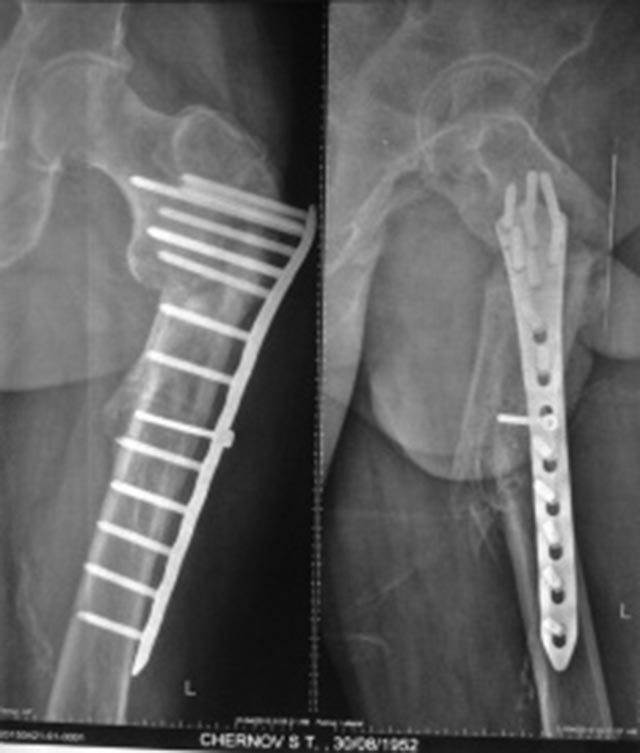

[Ortho] Ложный сустав вертельной области, варусная деформация

Дополнительные рентгенограммы